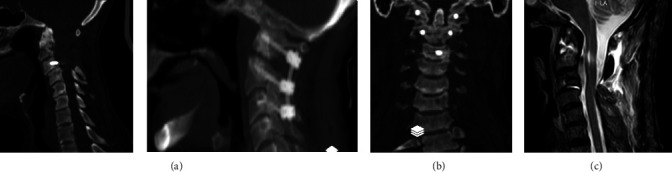

Background: Odontoid fracture (OF) is one of the most common spinal fractures. Type II in D'Alonzo's classification is still the most common and should be considered unstable unless proven otherwise. Thus, surgical stabilization has received significant attention. Although posterior displacement is common in type II OF, complete displacement is extremely rare, and very few reports are available in the literature. Case Presentation: We report the case of a 60-year-old man with acute type II OF with complete posterior displacement and myelopathy. The patient was managed utilizing a posterior-only single approach for reduction and stabilization. Conclusion: Posterior displacement of type II OF has been traditionally managed with close reduction and anterior or posterior stabilization. Closed reduction in cases of complete posterior displacement carries a significant risk of neurologic deterioration. Anterior, combined, and posterior approaches have been taken for this condition. The posterior-only approach in experienced hands has the least mortality and morbidity with at least the same neurologic and fusion outcomes.

Abstract Image